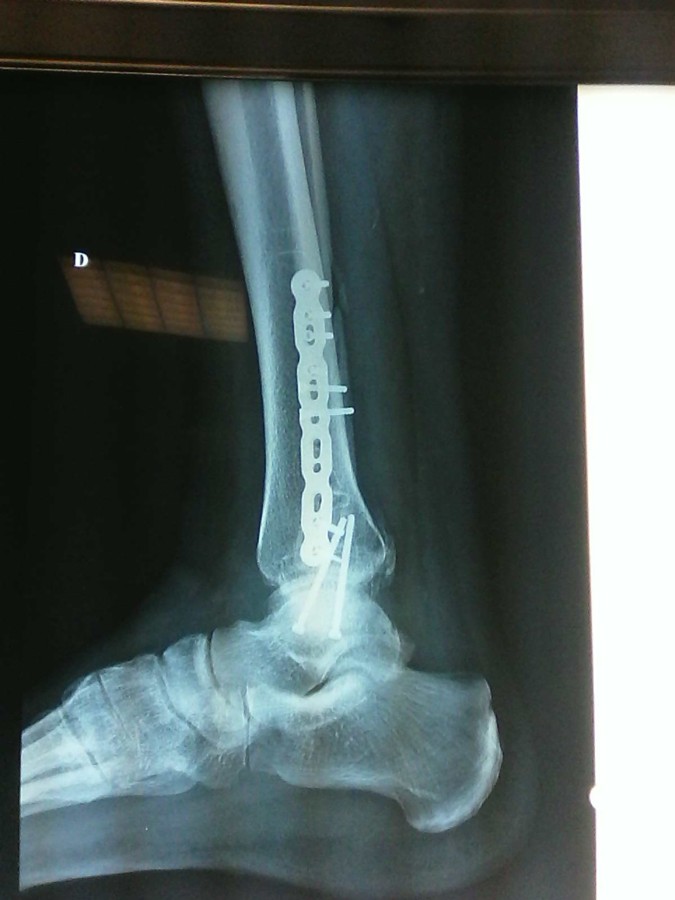

A la demande de Lucien 79, la samba des osselets !!!

Bien ferraillé le Lulu !!!

Bon courage pour la rééducation

moonarise a écrit :Justement, Jean-François...J'ai regardé!...Manquerait pas une petite vis tête fraisée entre la malléole interne et l'astragale?